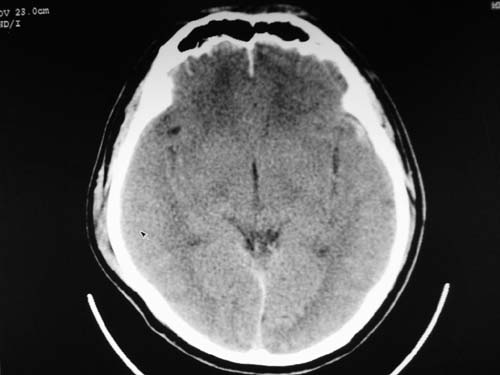

脑中线内血肿,是硬膜下的吗?

脑中线内血肿——硬膜下血肿。

脑中线内血肿——硬膜下血肿。我们一般认为中线即可是硬膜下,也可是蛛网膜下腔的。边缘锐利,张力高的考虑硬膜下的,边缘模糊的,考虑下腔的。如果有老师有肯定的答案,麻烦下给我发个短信

支持镰旁硬膜下血肿,颅骨骨折,头皮损伤.

这个病人年龄不小吧,右侧脑沟不清,中线结构稍有左移,右侧额颞顶及右镰旁硬膜下血肿,另有蛛血,骨折。

外伤后引起的颅骨骨折、硬膜下血肿、皮下血肿,颅骨骨折引起的矢状窦破裂,形成大脑纵裂内血肿。